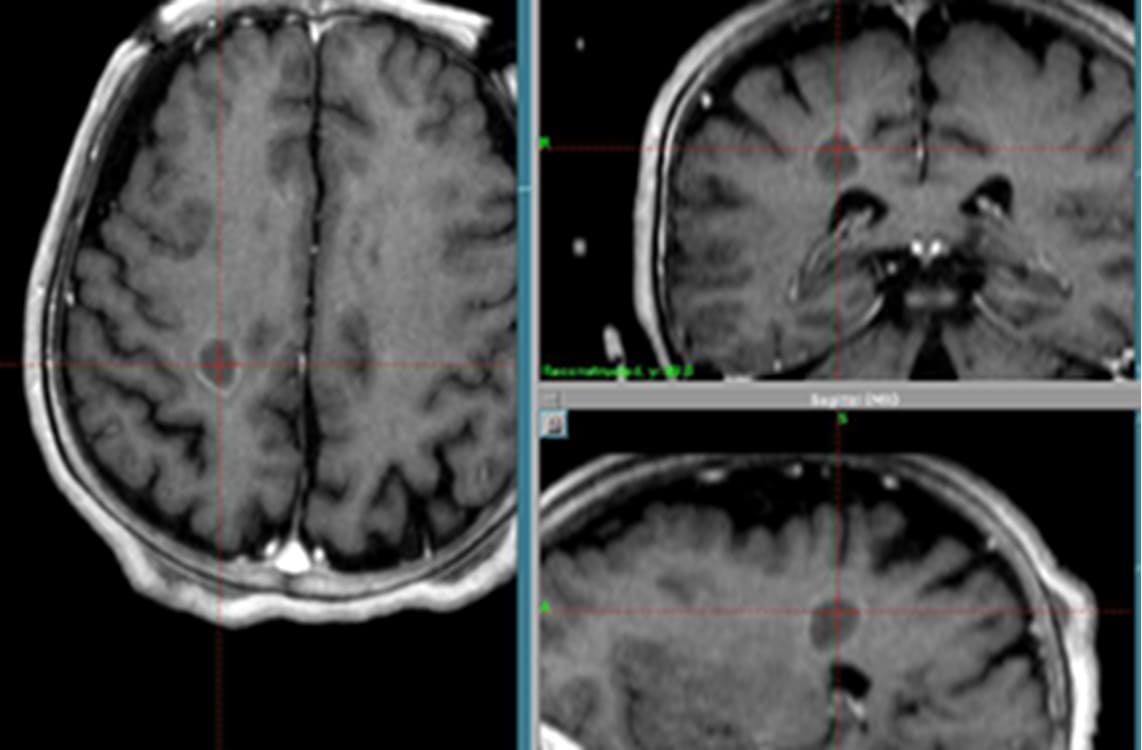

10か所ある多発性転移性脳腫瘍(乳がん)症例

実際の脳転移巣